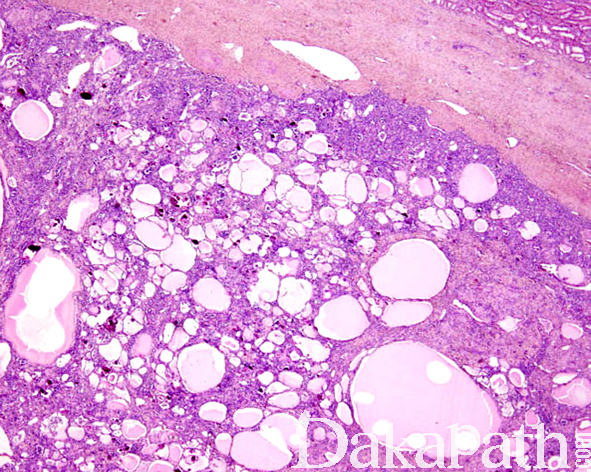

低倍镜下,病变整体上表现为致密排列的大小不等的囊肿或滤泡样结构,类似于甲状腺组织;滤泡样腔隙内充满嗜酸性分泌物伴吸收空泡样改变,被覆上皮呈扁平或萎缩状,亦可见明显的鞋钉样特征;部分滤泡样腔隙内可见漂浮的黏附性较差的病变细胞,与被覆上皮相比较,腔内的这些黏附性差的细胞较大,胞浆较丰富,核圆形为主,细胞之间有时可见致密的 PAS 阳性的嗜酸性物质围绕;

滤泡腔内和腔隙壁内常见多少不等的钙化物质沉积,分为两种类型:第一种类似于砂粒体样钙化,第二种为蓝染无定形的钙化物质;偶尔,某些滤泡壁内可见局灶的小的毛细血管样凸起,类似于萎缩的肾小球,PAS 染色凸起结构内的基底膜物质;罕见的情况下,可见肾小球囊性变的结构特征:Bowman 囊明显的囊性扩增,其内可见残存的不成熟的肾小球凸起,表面被覆扁平的内皮细胞;

囊肿或滤泡之间可见明显萎缩的肾小管、塌陷的肾小球以及胶原化间质,萎缩的肾小管腔隙狭窄、胞浆透明伴有 PAS 阳性的基底膜物质围绕。